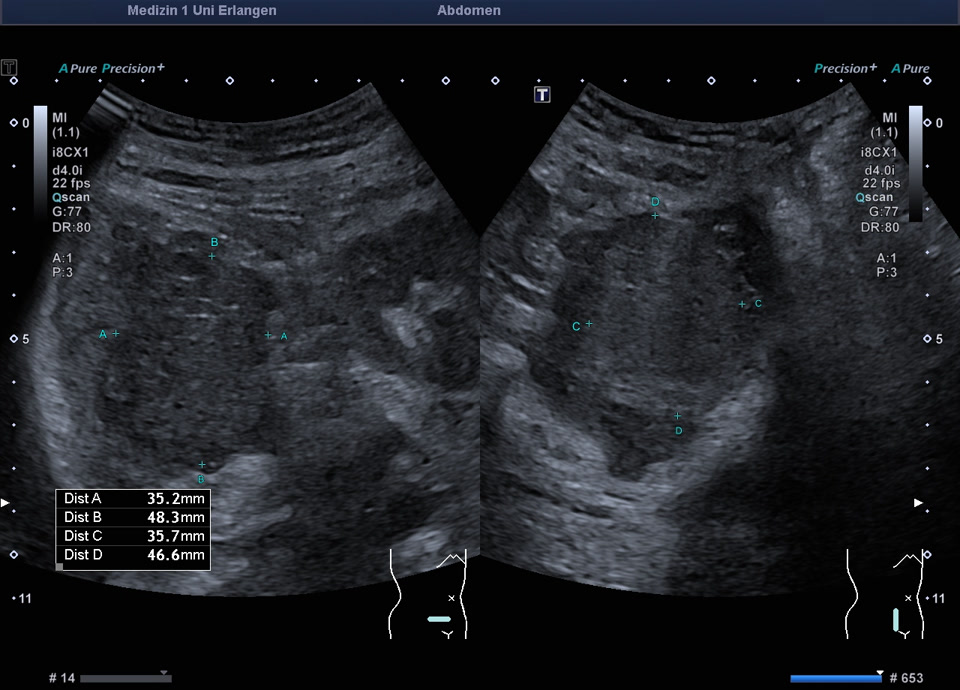

Retroperitoneum

• Psoas metastasis of urothelial carcinoma